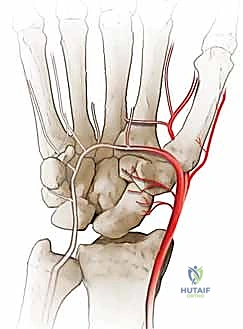

Crucially, the scaphoid's vascular anatomy plays a definitive role in its propensity for nonunion and dictates our surgical approaches. Taleisnik and Kelly meticulously described the intraosseous blood supply, highlighting its retrograde nature. The primary vascular contributors are the laterovolar and dorsal vessels.

Figure 2A: Volar intraosseous blood supply to the scaphoid, demonstrating the laterovolar vessels entering distal to the waist.

The laterovolar vessels enter the scaphoid at the level of the distal third and waist, supplying the distal pole and the volar aspect of the waist. Because the intraosseous vascular network courses from distal to proximal, fractures at the waist or proximal pole critically disrupt the blood supply to the proximal fragment, leading to avascular necrosis (AVN) in up to 30-40% of proximal pole fractures.